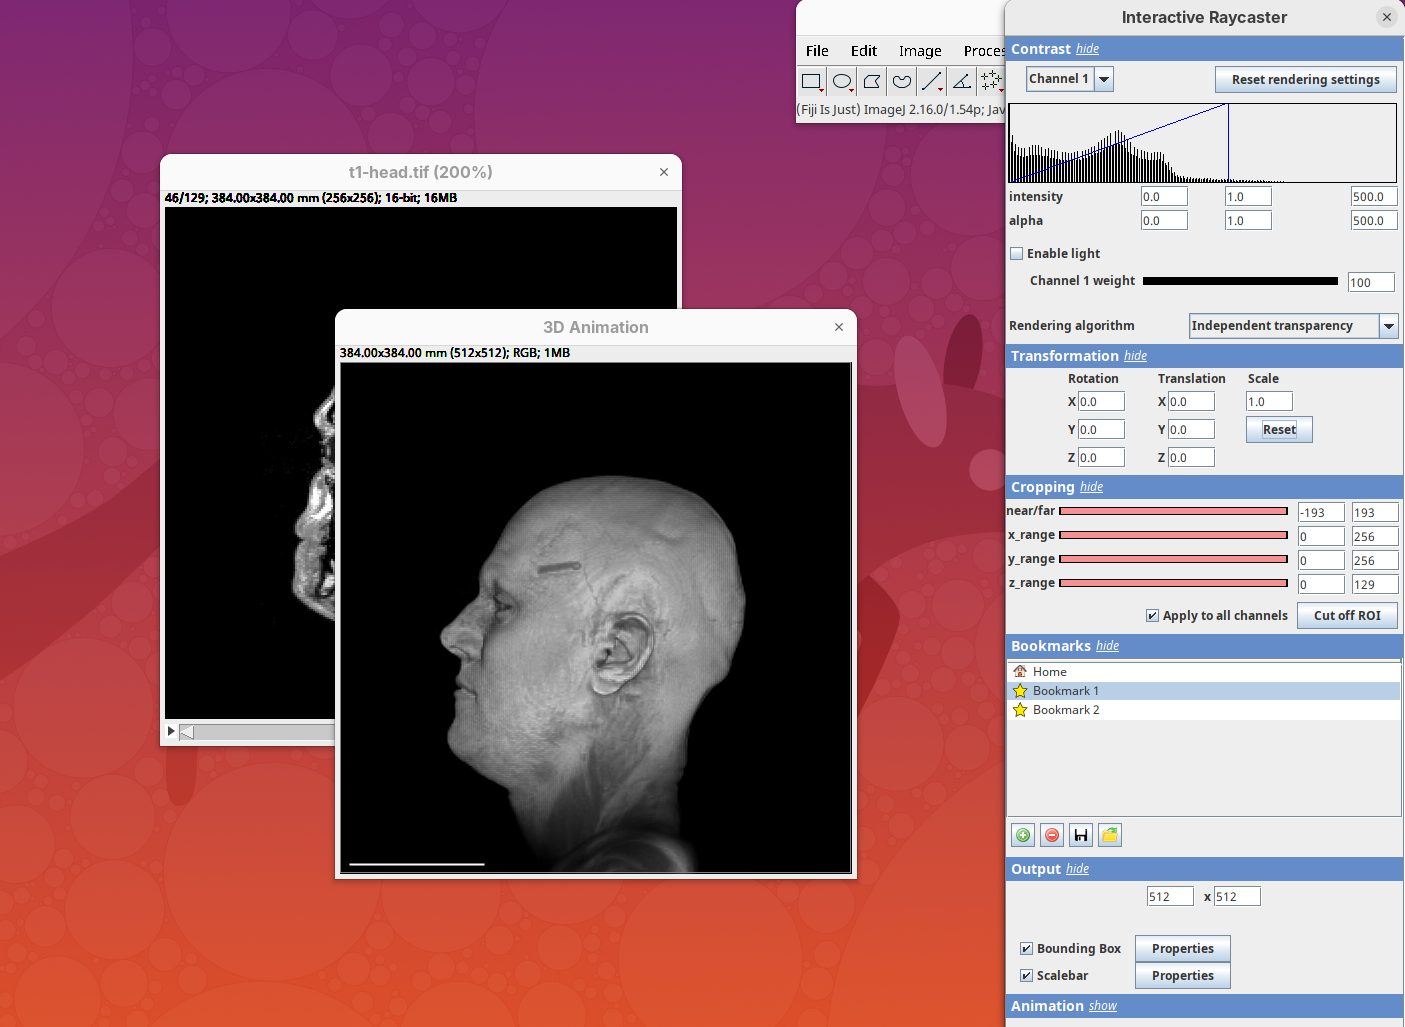

Output

This last panel defines the dimensions of the output animation. By default it uses the original stack dimensions.

You can also define if the bounding box or the scale bar will be visible (enabled by default).

Animation 3D

Now that we learned the basics of setting up the rendering and view parameters, we can start generating animations of the data.

- Click on the

Animationsection and on theStart text-based animation editorbutton.